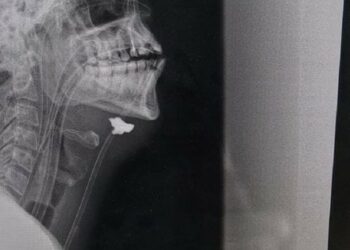

Kardiochirurgovia v Kyjeve vykonali jedinečnú operáciu obrancu s ťažkým poranením srdca

Národný inštitút kardiovaskulárnej chirurgie Mykola Amosov prvýkrát na svete vykonal jedinečnú operáciu 49-ročného vojaka z regiónu Vinnytsia, ktorý utrpel vážne ...